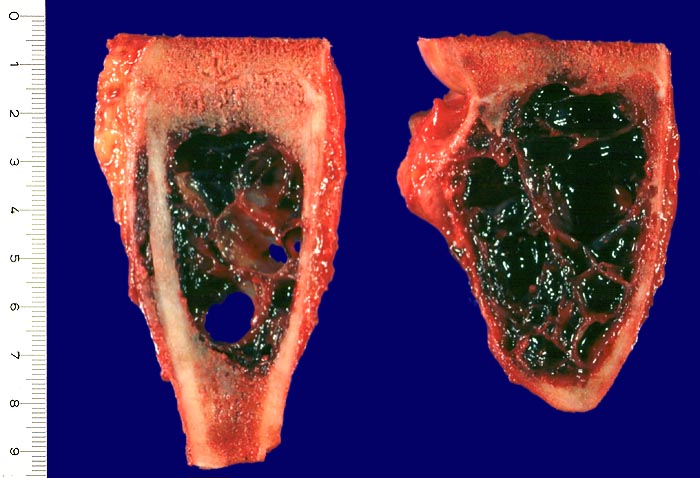

Die aneurysmatische Knochenzyste zählt zu den gutartigen tumorartigen Läsionen. Sie ist eine schnellwachsende, lokal aggressive, intramedullär gelegene Läsion, welche zu einer Knochenauftreibung führt. AKZ können primär oder sekundär auftreten (zusammen mit einem Chondroblastom, einem Chondromyxoid Fibrom, einem Riesenzelltumor, einer fibrösen Dysplasie oder einem Osteosarkom (> 2090)).

Radiologisch (> 5034) (> 5036) (> 5035) führt die AKZ zu einer exzentrischen scharf begrenzten gekammerten Osteolyse mit verdünnter vorgewölbter Kortikalis im Bereich der Metaphyse, seltener der Diaphyse. Die Therapie besteht in der Kurettage.

Makroskopie